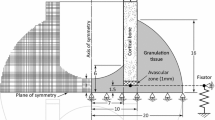

Studies have shown that each device produces a specific pattern of strain through the cortex at the screw-bone interface as shown in Fig. 3 [13, 29, 34]. Mono-lateral devices and locking screws (Figs. 3bb, c) induce large strains that penetrate the full cortical thickness particularly in bone of poor quality [29]. In Ilizarov and far-cortical locking fixation, however, strain localisation is at the periosteum and endosteum and does not penetrate the entire cortical thickness (Fig. 3aa, d) [13]. Device asymmetry and offset from the bone affect the stiffness of the construct. Although Fig. 3aa shows a bone centrally positioned between the supports at the mid-span of the wire, this is rarely possible as a prohibitively large ring would be required [16]. Asymmetric positioning of Ilizarov devices is known to increase their stiffness, due to a decrease in wire length to the support [7]; however, it also causes greater stress on the cortex closer to the ring. Similarly, when using mono-lateral devices, increasing offset from the bone has an approximately linear increase on screw-bone interface stress [4].